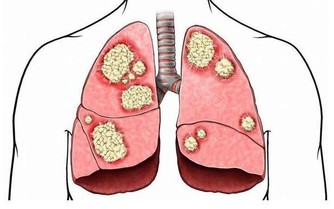

肥胖真的超燒錢!肥胖有可能是你花了很多錢吃喝,也有人會花很多錢來減肥,肥胖甚至會引起很多疾病,而且去治療這些疾病,健保還得給付;醫界更預估,到了2020年時,健保預算的1/3是用來給付因為肥胖所引起的疾病。 高血壓+高血脂+糖尿病+心血管疾病+癌症 有哪些疾病是因為肥胖所引起、會需要用到健保來看病的呢?天主教聖馬爾定醫院家庭醫學科主任陳志誠指出,肥胖會出現代謝症候群,進而引起高血壓、高血脂、糖尿病,並且也會造成心血管的問題,肥胖甚至會增加一些癌症的風險,例如大腸癌及乳癌,肥胖都是危險因子。 退化性關節炎+對磨疹+淋巴水腫+睡眠呼吸中止症 陳志誠主任進一步指出,肥胖還會使得膝關節和髖關節負擔大,以致出現退化性關節炎,皮膚也會因為容易在皺摺處引起對磨疹或是感染,增加淋巴性水腫的可能性,肥胖更可能產生睡眠呼吸中止症,影響睡眠品質。 成人過重及肥胖盛行率為38% 根據世界衛生組織研究報告顯示,全球有將近1/3成人、1/4孩童過重,總計目前全球肥胖或過重的人口超過21億。而根據衛福部所進行的2013年「國民營養健康狀況變遷調查」結果顯示,成人過重及肥胖盛行率為38%;也就是說,不到三個成年人中,就有一人過重或是肥胖;醫界並預估,到2020年時,將有1/3健保預算,會用來給付因為肥胖所引起的相關疾病診療費用。。 飲食與運動是減重不二法門 因此,減重除了能改善體態之外,更重要的是能預防諸多疾病,而飲食與運動則是減重的不二法門;陳志誠主任則是強調,減重要成功,其關鍵就是要先找到自己想改變的原因,而且慢慢的把不好的習慣一個一個改過來,不求速效,而是考慮可以維持多久! 健康醫療網: http://www.healthnews.com.tw/news/article/29601